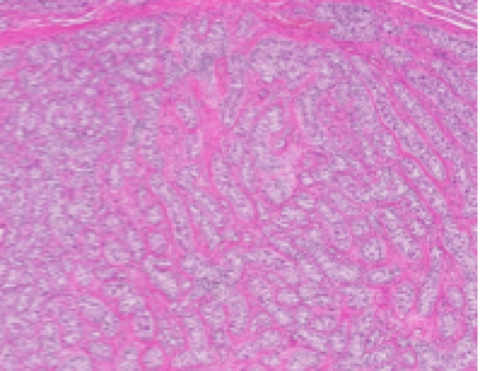

セルトリ細胞腫は組織形態に基づいて管内型とびまん型に分けられ、精細管内に留まる管内型から基底膜を侵襲してびまん型に進行していきます。通常、腫瘍細胞は精細管内に存在するセルトリ細胞に類似した形態を示し、豊富な成熟した線維性結合組織で構成される間質の増生が特徴的に見られ、腫瘍細胞は島状あるいは索状構造を形成して増殖します。腫瘍細胞は円柱形から紡錘形で、核は類円形から紡錘形で、泡沫状から空胞状の好酸性細胞質を有します。管内型では、腫瘍細胞は精細管基底膜に対して垂直に柵状に配列するのが特徴的で、びまん型では管状構造は不明瞭となり、密な線維性間質によって区画された広いシート状あるいは島状構造を形成して増殖します。びまん型の腫瘍細胞の形態は不整となり、精巣周囲組織へ浸潤し、脈管浸潤を伴う場合があります。

セミノーマは組織形態に基づいて、管内型とびまん型に分けられます。管内型は初期の組織形態であり、精細管内で精細胞様の腫瘍細胞が精細管内の構造を置換して増殖します。腫瘍組織による精細管の破綻は比較的すぐに起こり、腫瘍細胞の敷石状、充実性増殖病変を形成し、びまん型へ進行します。腫瘍細胞は大型類円形から多角形であり、好塩基性または好酸性細胞質を有し、核は大型円形で1~複数個の明瞭な核小体を含有し、核分裂像が多く観察されます。CD8陽性のリンパ球の集簇巣が多くの腫瘍にみられます。散在性にみられる個々の腫瘍細胞の壊死は、腫瘍組織内で星空像を呈します。